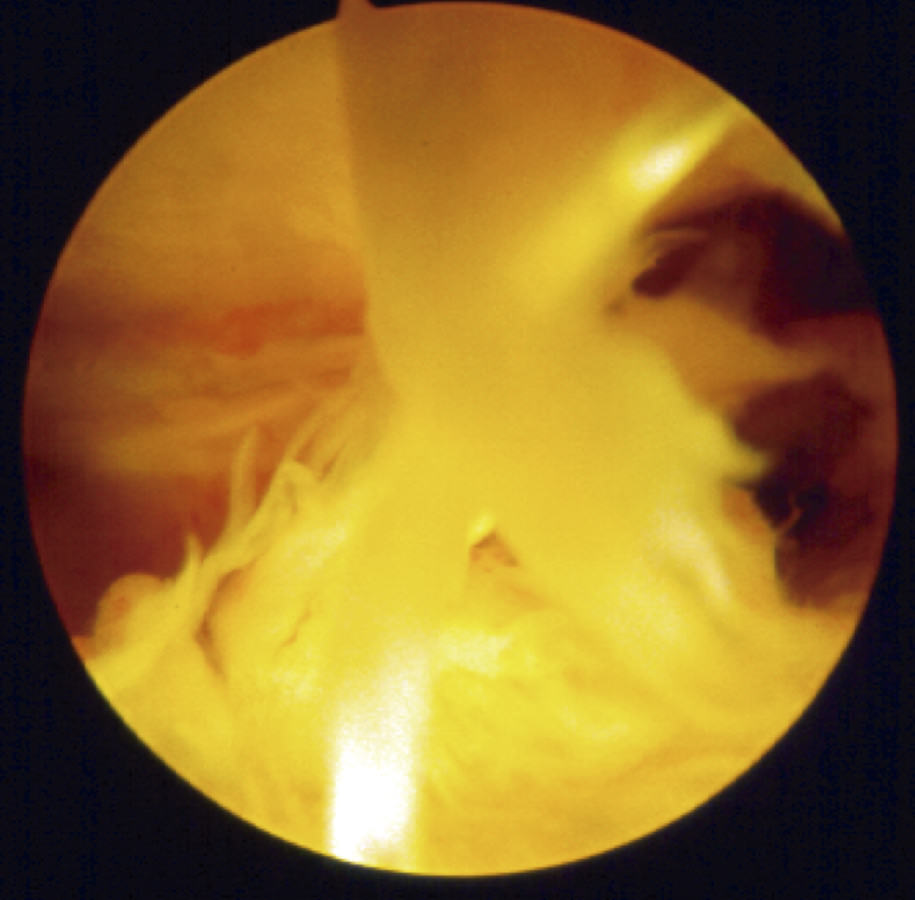

Siguiendo por los recesos lateral y medial (Figura 5) se llega a la zona suprapatelar, cuya fibrosis es la primera causa de limitación de la flexión (Figura 6). En este espacio hay que ser muy meticuloso para resecar con motor (Figura 7) y radiofrecuencia las adherencias, los nódulos, cíclopes (Figura 8), la fascia profunda del cuádriceps, con esqueletización de la cara anterior de fémur si es necesario, y liberar el alerón externo e interno, en función de la rótula: si está lateralizada (liberación solo lateral) o bien centrada (liberación lateral y medial), para facilitar el recorrido rotuliano. La limpieza de este espacio es fundamental para recuperar el máximo grado de flexión.

Figura 6. Bandas fibrosas articulares con disfunción patelofemoral y dolor anterior en prótesis de rodilla.